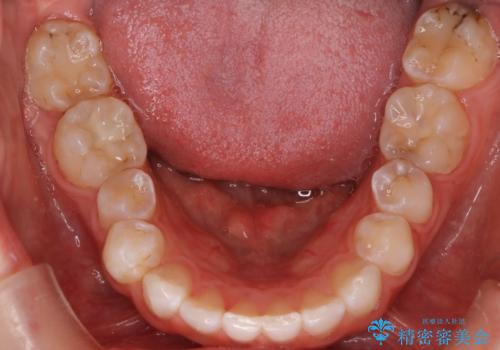

- 右上の八重歯と歯のデコボコ、そして上下の歯の中心(正中)のズレを気にされて来院されました。精密な検査の結果、歯が並ぶスペースが不足しているため、上顎の小臼歯(前から数えて4番目の歯)を抜歯し、そのスペースを利用して歯並び全体を整える治療計画を立案しました。これにより、八重歯の位置を適切に改善し、叢生(歯のデコボコ)を解消するとともに、上下の正中線のズレも改善することを目指します。

今回の矯正治療では、歯が並ぶスペースを確保するため、上顎の小臼歯を抜歯しました。抜歯によってできたスペースを有効活用し、ワイヤーやブラケットを使って右上の八重歯を適切な位置へ移動させ、叢生を解消していきました。また、治療を通じて上下の歯の中心である正中線のズレも改善するよう、慎重に歯を動かしました。治療の結果、長年気にされていた八重歯と歯のデコボコが解消され、上下の正中線も一致。機能的にも審美的にもバランスの取れた、美しい歯並びと笑顔を獲得していただけました。